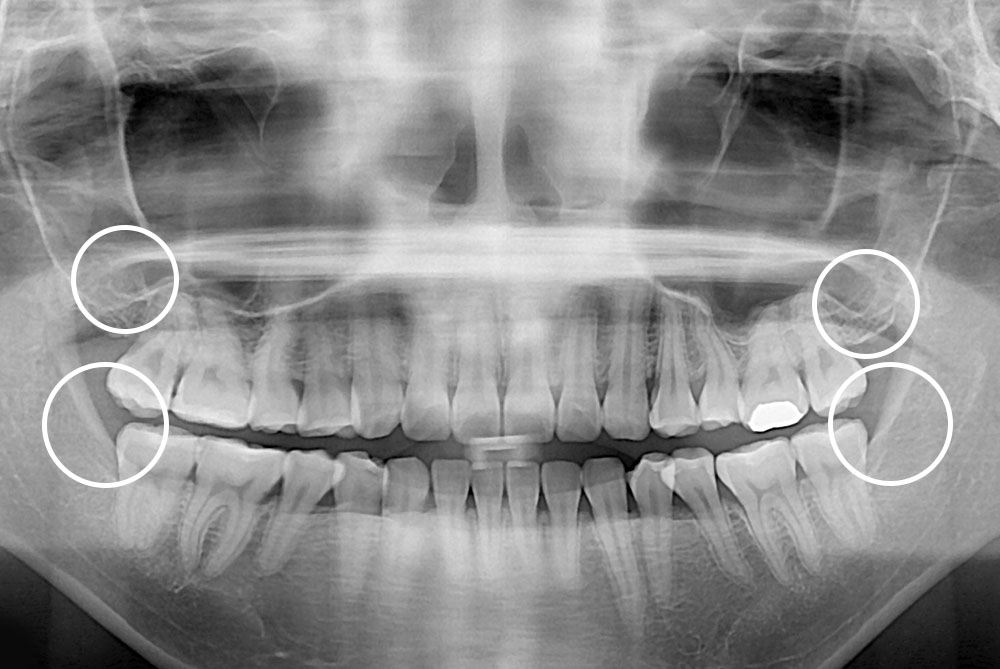

[사랑니] 매복 사랑니 발치

치료전 : 2017-09-07